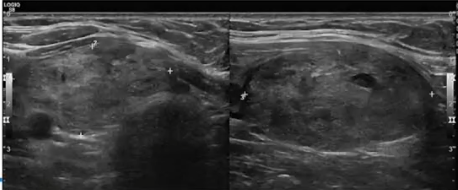

![]() ![]() 20ml 症状评分=8;美容评分=4